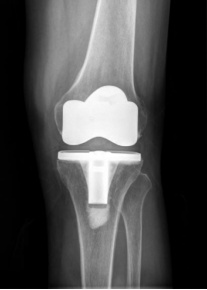

⑤ 人工关节表面置换术:俗称“换膝”手术,是20世纪最成熟的手术方式之一,已成为严重膝骨关节患者的救星。通过对膝关节的表面进行精确的截骨矫形,安装上寿命20年以上的人工关节假体,让历经磨难的膝关节焕然一新,返老还童。由于手术风险低,效果好,对于50岁以上患有膝关节骨关节炎,生活质量受到严重影响的患者非常适用。